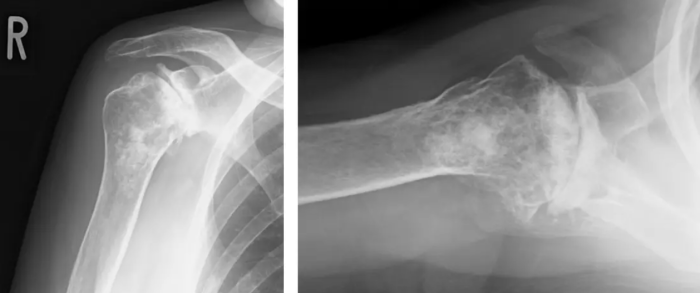

X-ray before surgery

Coronal CT

A deeply concave glenoid